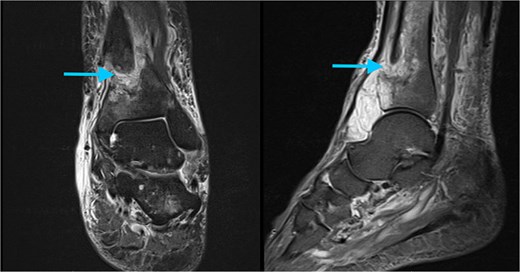

During the preoperative evaluation, computed tomography demonstrated erosive changes of the anterior tibial cortex with associated swelling of the anterior compartment. On further history, the patient reported several weeks of painless anterior ankle swelling prior to the injury and denied constitutional symptoms. These findings raised concern for a pathologic fracture, prompting further evaluation with magnetic resonance imaging prior to operative intervention (MRI). MRI demonstrated a well-circumscribed soft tissue lesion with high T2-weighted signal intensity adjacent to the anterior distal tibial cortex (Fig. 2). Based on these findings, operative fixation with concurrent lesion excision was planned.

Preoperative MRI of the left ankle. Axial T2-weighted images demonstrate a well-circumscribed, hyperintense soft tissue lesion adjacent to the anterior cortex of the distal tibia (arrow).